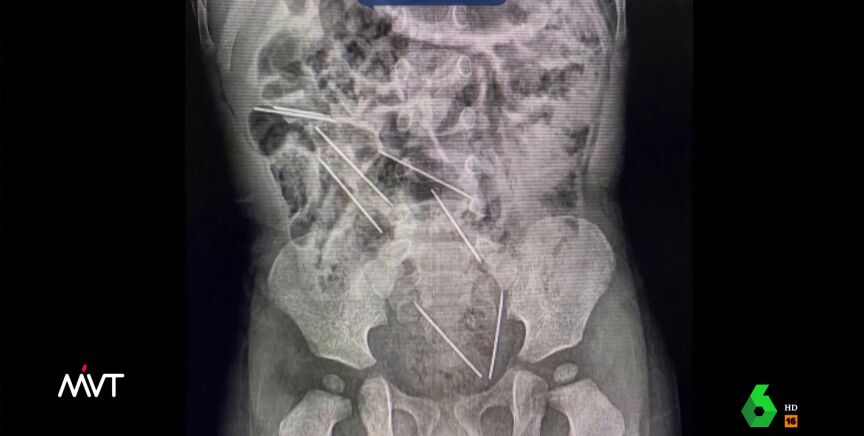

Un niño de dos años se traga ocho agujas para vacas en Perú y es intervenido de urgencia

El niño ingirió las ocho inyecciones mientras jugaba en la finca donde trabajaba su madre. El pequeño fue operado de urgencia y se recupera rápidamente.

Un pequeño de dos años se tragó ocho inyecciones para vacas en Perú. Los médicos lograron actuar con rapidez y sacárselas del estómago y del tracto intestinal a través de una operación de urgencia.

El pequeño, que permanece en el hospital ingresado, se recupera rápidamente, según han avanzado los médicos al citado medio.